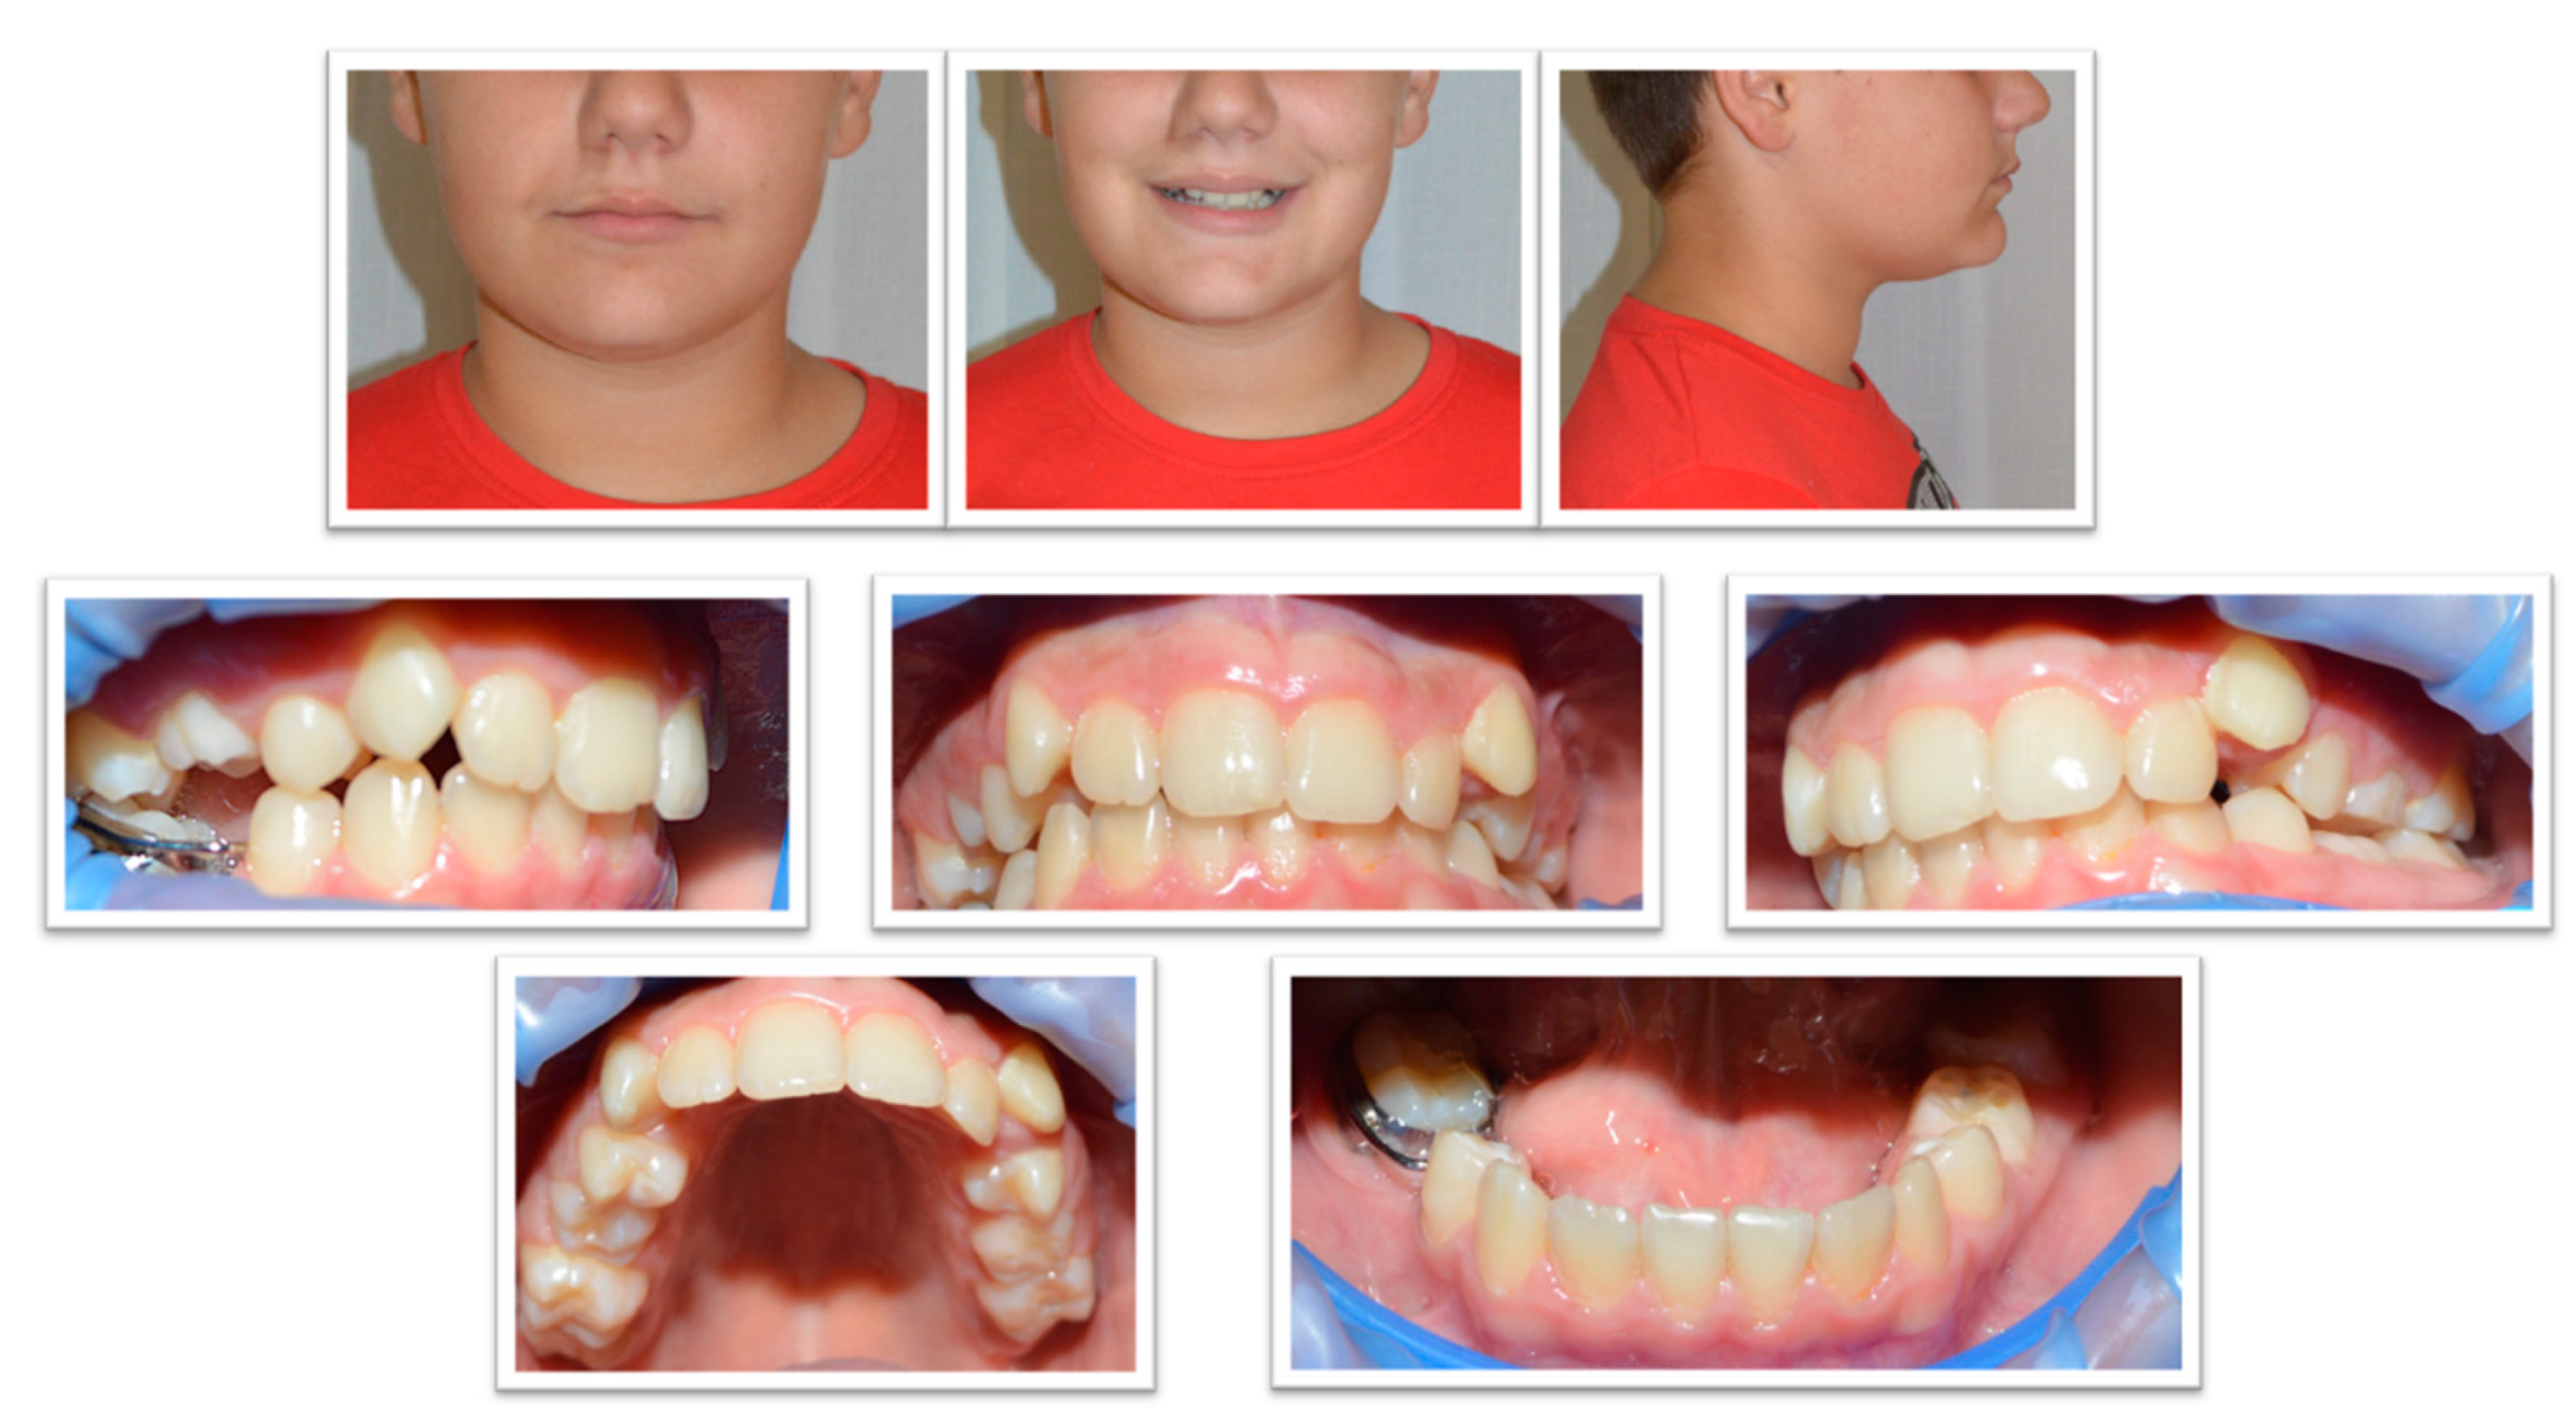

2. Case Report

2.1. Examination, Diagnostics, and Initial Therapeutic Management

2.2. Treatment Plan

2.3. Treatment Progress